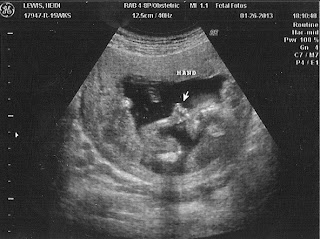

I had an ultrasound done that week. Dr. Smith likes to start my prenatal visits early because of my history, for which I am grateful. And honestly, I was expecting no heartbeat at this ultrasound... if we were following a pattern, another miscarriage would be in tow. There was one before Jack, one before Zy, so that's what I expected for this one. And, for the first five minutes or so, she couldn't find one. There was a baby; it's amazing the detail you can see in something so tiny. I love seeing the spine. It's always so intricate and detailed. Incredible.

Because she wasn't finding a heart beat, I was building myself up for the worst. She wanted to do an ultrasound inside, to get a better look - and it wasn't long before we saw that beautiful little flutter in that tiny frame on the screen. I was even able to hear it - which is one of my favorite sounds in the entire world.

At this point, 12 weeks, nobody in my family knew I was pregnant. I had told a few people at work, and Chris had told a couple of friends, but we had always wanted to find out the sex of the baby before telling our families we were pregnant. That was our goal this time around. At Fetal Fotos, 15 weeks was the earliest we could find out, so we decided to pay the extra money there to get a gender check.

Well, not long into the ultrasound, and, like a true Lewis boy (his brothers were the same), there was no mistaking about what was there. He was not shy about "showing" himself. I was right!

The next night, we decided to hand Jack the envelope of the ultrasound pictures for him to open for his first gift after having dinner and had everyone gathered together. He and Zy came with us to Fetal Fotos, so he knew what they were and what he was looking at. He pulled out the pictures, and right away said, "BABY!" while we waited for everyone's reactions. That was something they were NOT expecting. It took everyone a few seconds to get it, it was great. They couldn't believe I was having another boy, let alone that I was pregnant. It was a fun surprise and fun way to announce our third boy!